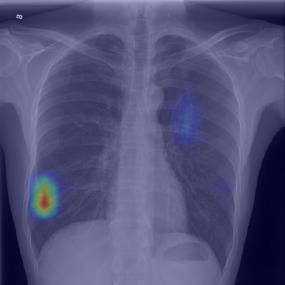

Chest X-ray (CXR) is the most typical diagnostic X-ray examination for screening various thoracic diseases. Automatically localizing lesions from CXR is promising for alleviating radiologists' reading burden. However, CXR datasets are often with massive image-level annotations and scarce lesion-level annotations, and more often, without annotations. Thus far, unifying different supervision granularities to develop thoracic disease detection algorithms has not been comprehensively addressed. In this paper, we present OXnet, the first deep omni-supervised thoracic disease detection network to our best knowledge that uses as much available supervision as possible for CXR diagnosis. We first introduce supervised learning via a one-stage detection model. Then, we inject a global classification head to the detection model and propose dual attention alignment to guide the global gradient to the local detection branch, which enables learning lesion detection from image-level annotations. We also impose intra-class compactness and inter-class separability with global prototype alignment to further enhance the global information learning. Moreover, we leverage a soft focal loss to distill the soft pseudo-labels of unlabeled data generated by a teacher model. Extensive experiments on a large-scale chest X-ray dataset show the proposed OXnet outperforms competitive methods with significant margins. Further, we investigate omni-supervision under various annotation granularities and corroborate OXnet is a promising choice to mitigate the plight of annotation shortage for medical image diagnosis.